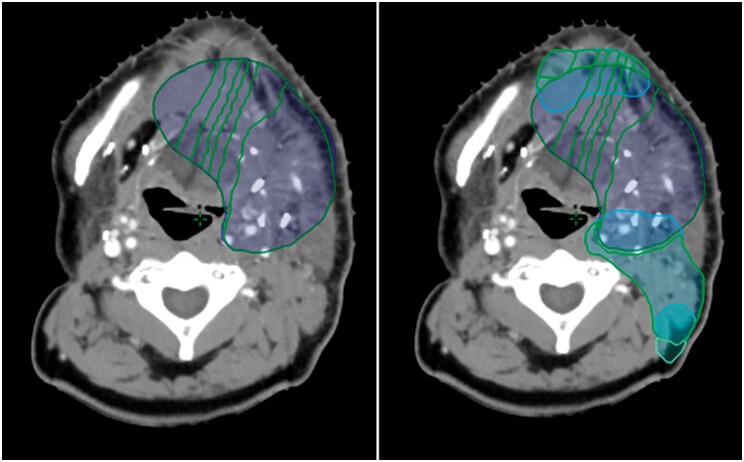

Abstract Image